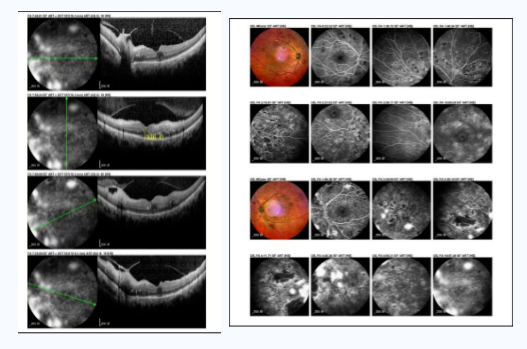

宋主任听完并对张大爷做了基础检查后,判断他可能是糖尿病视网膜病变,并为他安排了详细检查。在进行了眼底血管造影、后节OCT等相关检查后,结果显示,张大爷不仅双眼糖尿病视网膜病变,还伴有左眼黄斑水肿。除眼科疾病外,张大爷的随机血糖竟高达17.9mmol/L。宋主任建议他先内分泌科,等血糖控制稳定后再进行玻璃体腔注药手术治疗。手术后一月复查,张大爷的病情有所改善。